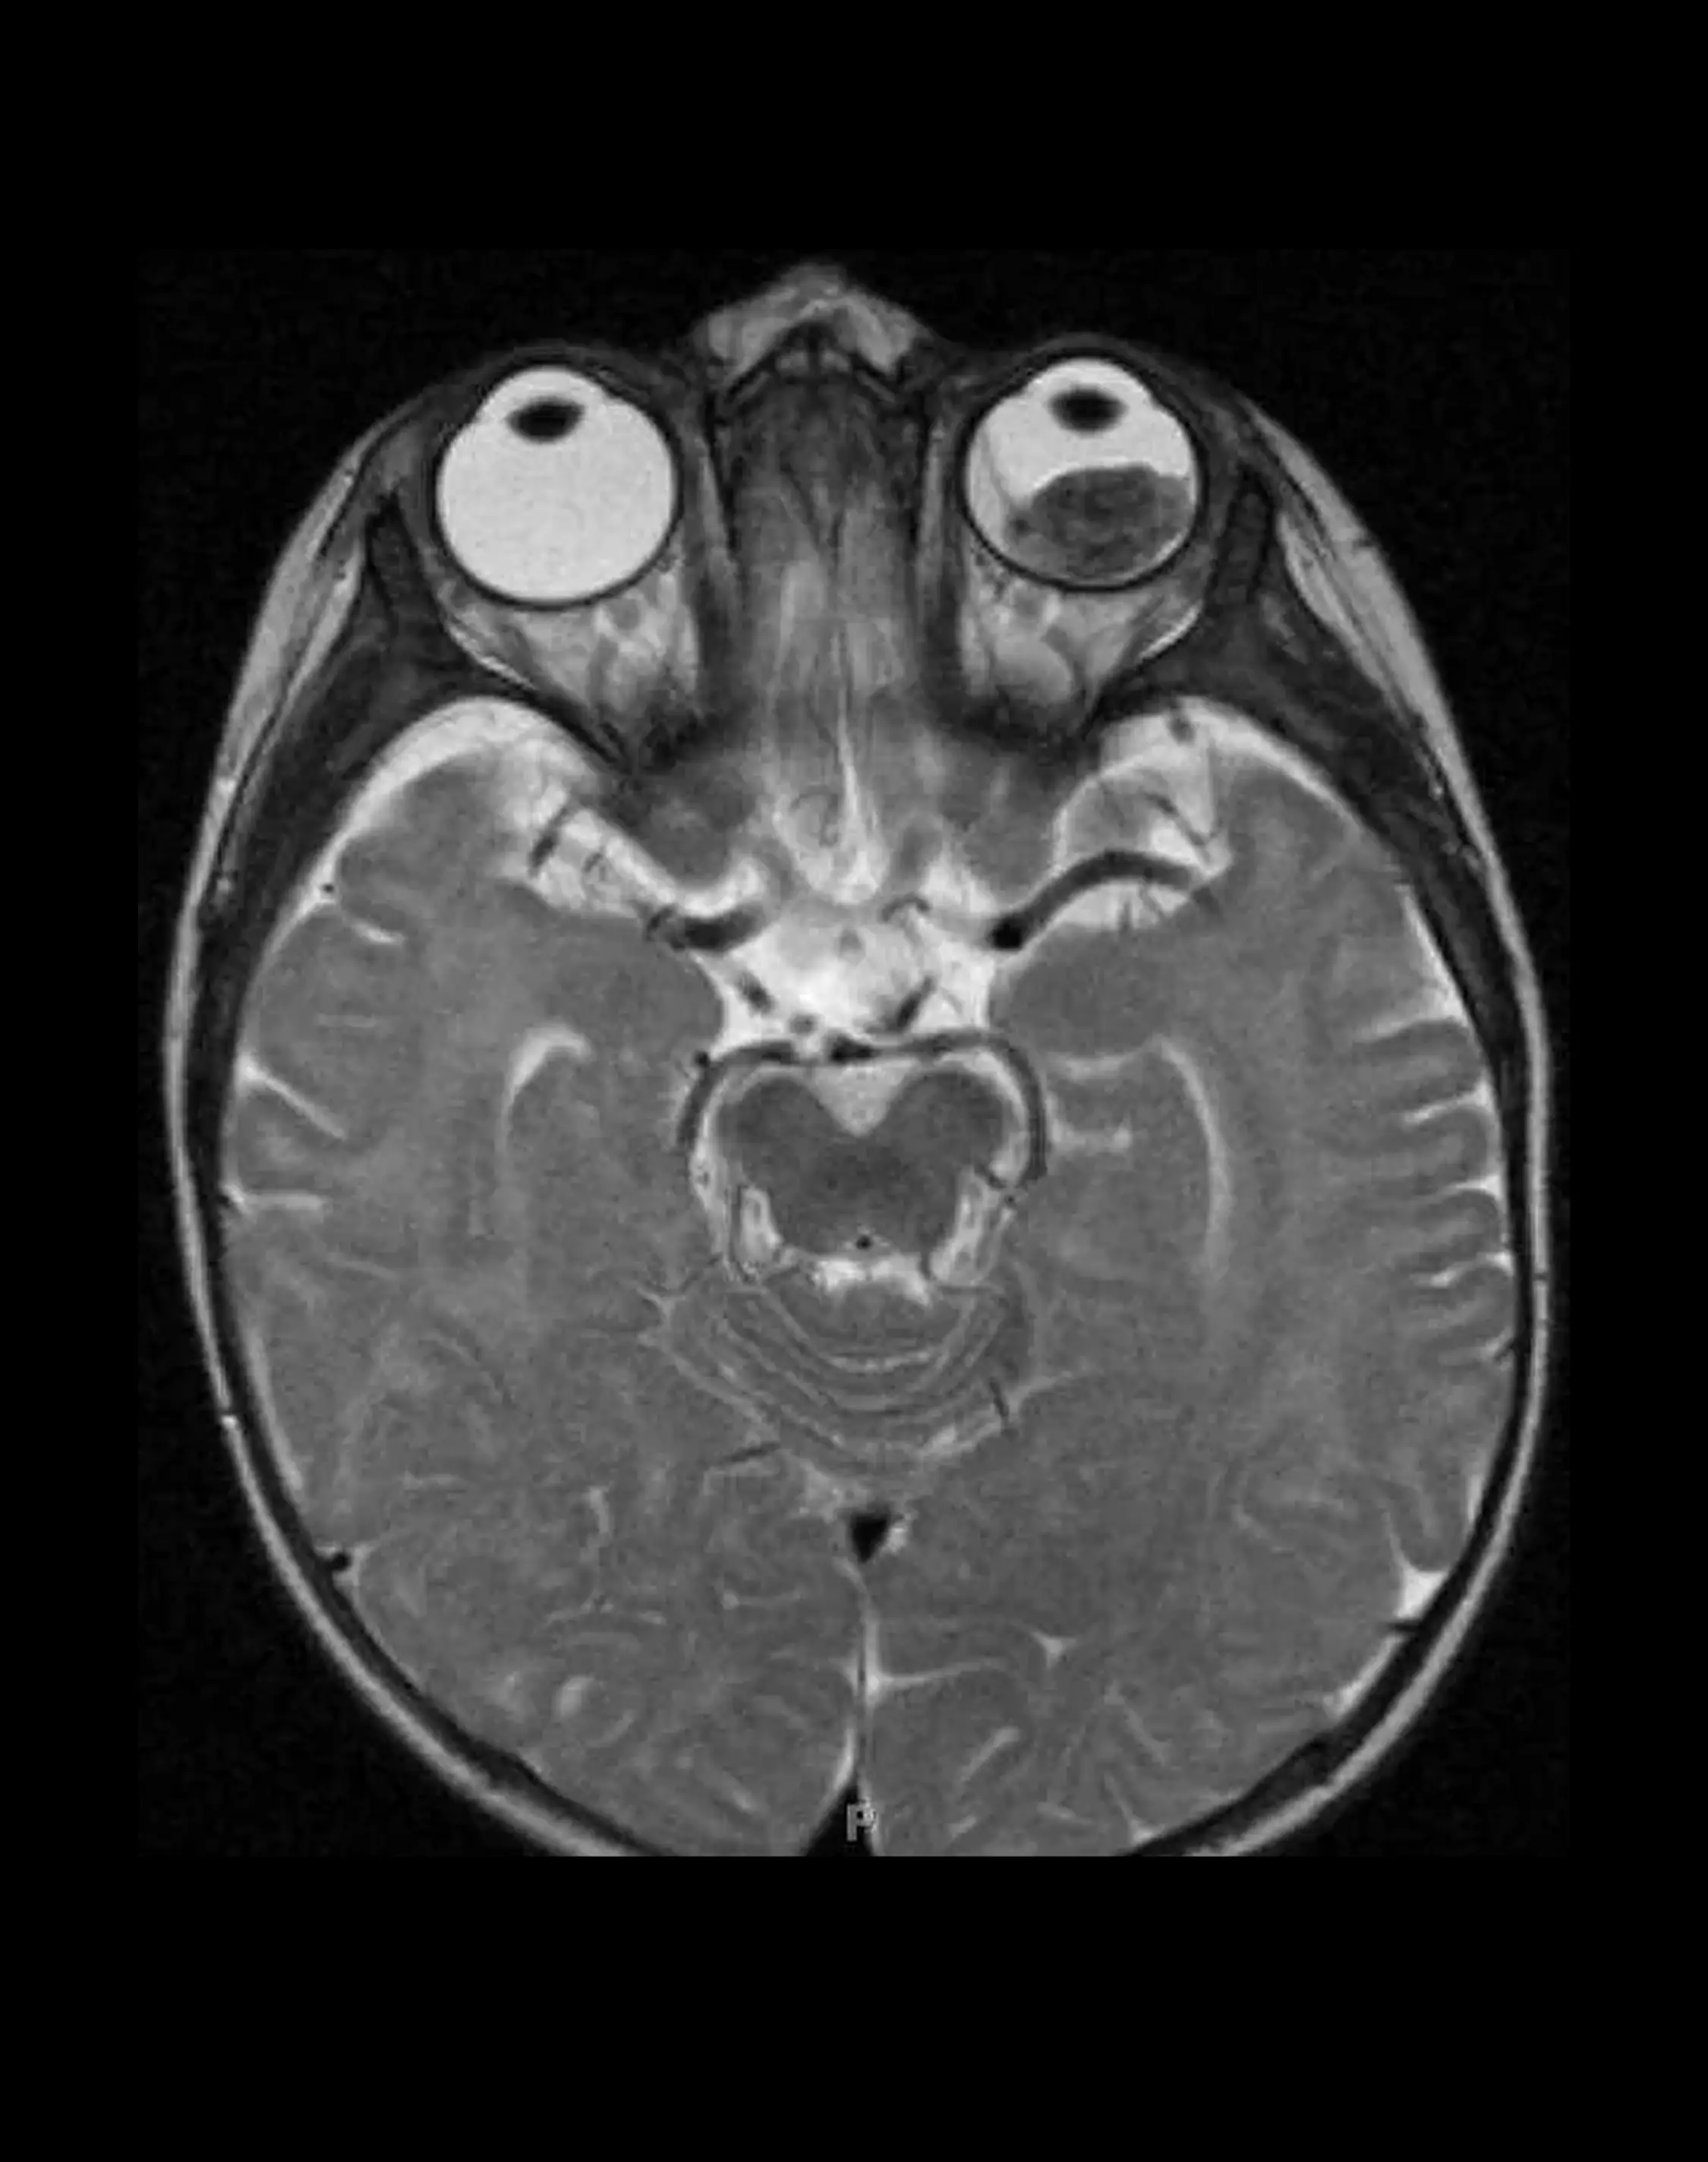

МРТ орбит (глазных яблок)

Получение изображений глазных яблок, зрительных нервов, глазодвигательных мышц, ретробульбарной клетчатки, зрительного перекреста, слезной железы и прилежащих структур.